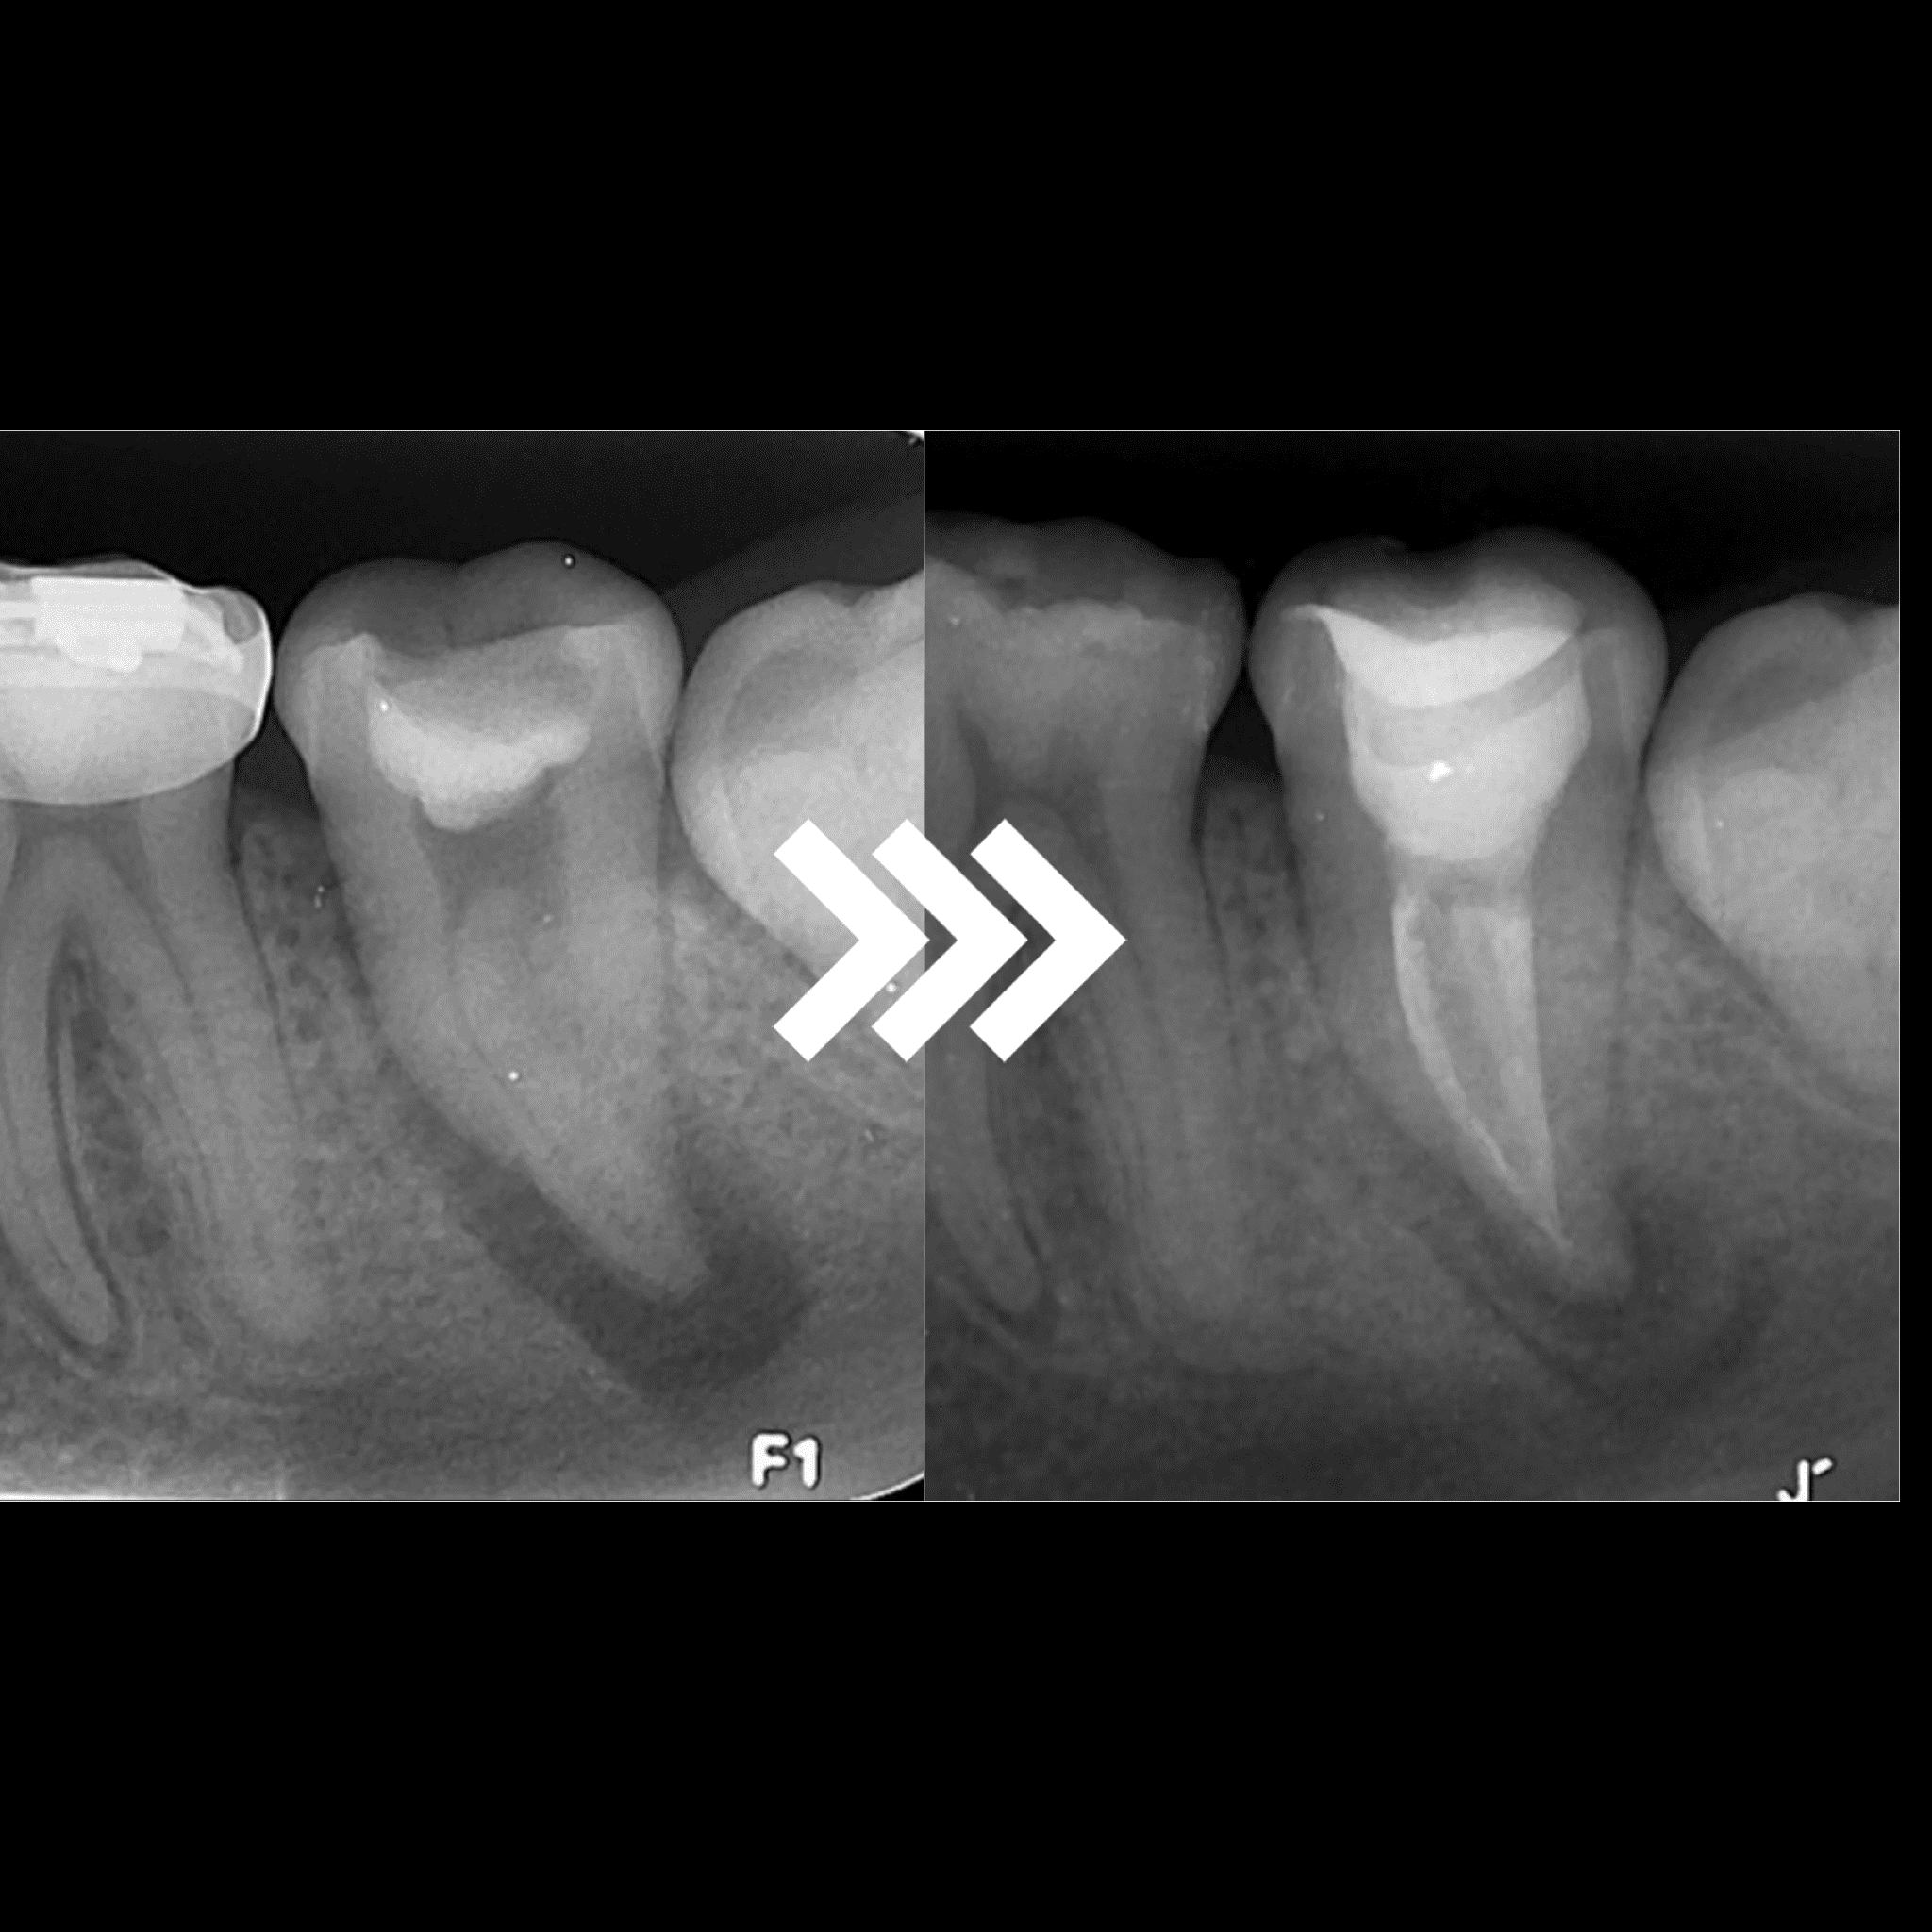

Durante esta consulta especializada, nuestro equipo de endodoncistas altamente capacitados se dedica a evaluar, diagnosticar y ofrecer soluciones para problemas relacionados con la pulpa dental y las infecciones de la raíz.